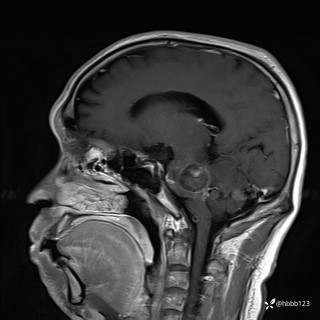

患者男,51岁。

简要病史:患者自述于1周前至某人民医院发现脑干肿瘤(具体不详),为求进一步诊断至我院就诊。

完善颅脑MRI平扫+增强,颅脑CT平扫:

T1增强矢状位重建: